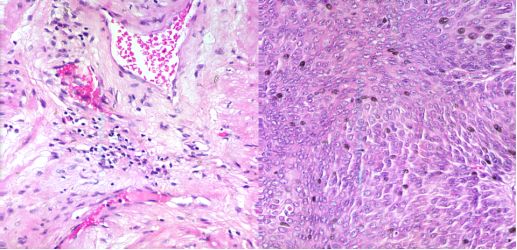

1.2.显微高光谱在血细胞检测的应用

血细胞分类在诊断学中作用巨大。例如,细胞谱相的识别与某个特定的疾病相关联,以及白细胞的计数已被证明与多种疾病相关联,包括肥胖、吸烟、过敏性哮喘等。最初,血细胞分类与计数在显微镜下手工进行,这样不仅费时,而且错误率较高。自动血细胞分类能在数字显微成像技术下实现。由于不同类型的血细胞形状相似,细胞分类的准确性和特异性仍然对传统的显微成像技术造成挑战。医学高光谱图像将二维空间图片与一维光谱信号合并为一个三维数据立方体。结合光谱和成像技术,医学高光谱图像的本质是反映材料以及在分子级别的电磁波下如何吸收和反射光线。它不仅包括丰富的空间信息,更包含许多称之为光谱特征的连续窄波段,这样能够准确地区分不同的血细胞。目前,医学高光谱成像技术已应用于舌肿瘤、肠道缺血及癌症、出血性休克、医疗食品安全以及其它诊断学的检测、/p>

医学高光谱图像数据库的不同波长的波段

(a)背景、白细胞和红细胞伪彩色图像;(b)实际分布国/p>